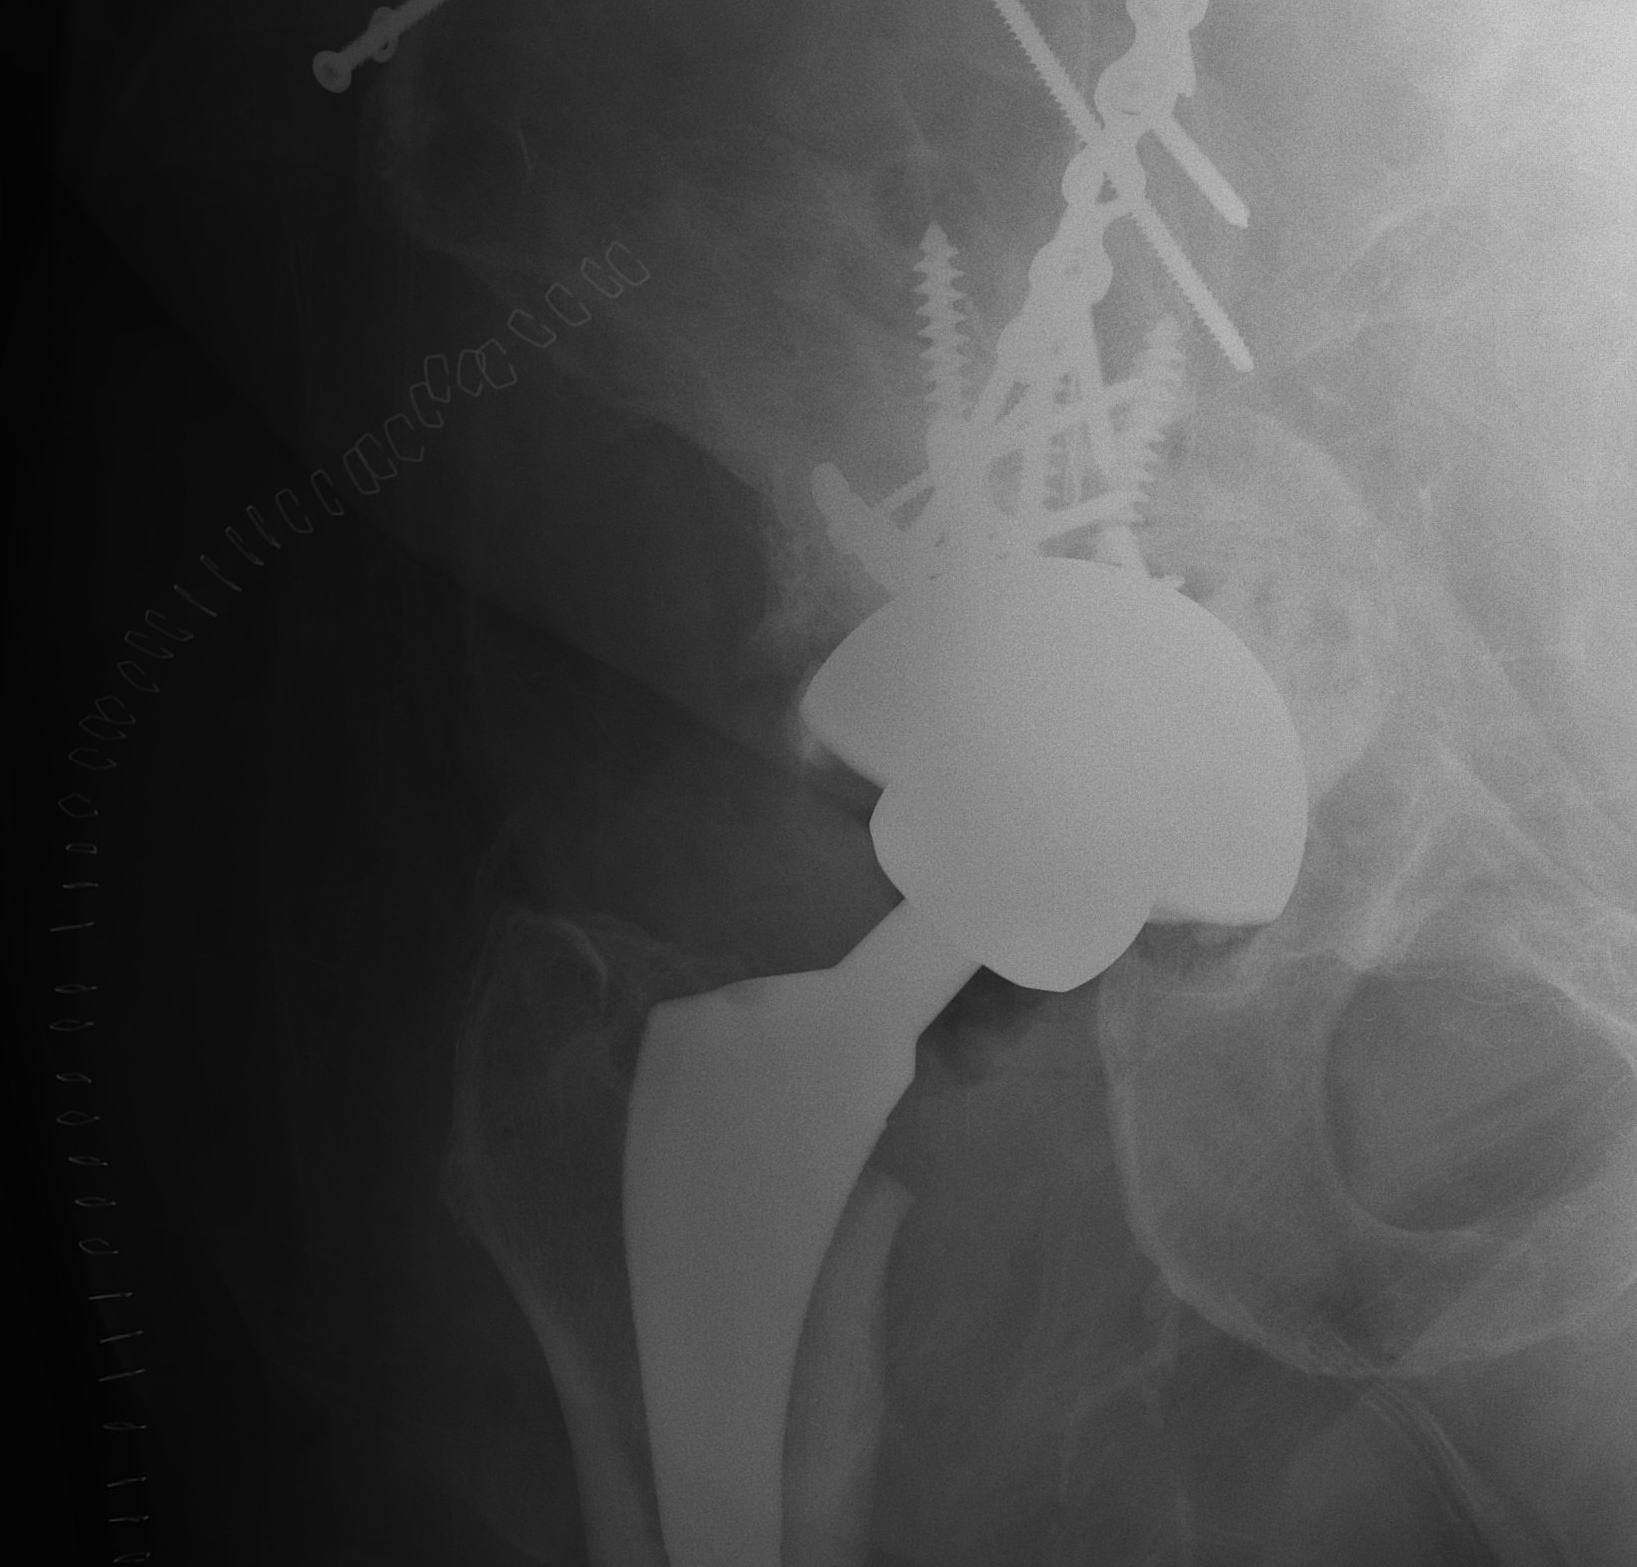

ORIF

1. Reduce quadrilateral plate

- small T plate / will sit under pelvic reconstruction plate

- separate recon plate

2. Plate iliac crest fracture

- long 13 hole plate from pubis

- along superior pubic ramus up onto inner table of ilium

- indirect acetabular reduction

Failure of fixation

Very problematic

- often need revision to THR

- pelvic discontinuity must be addressed